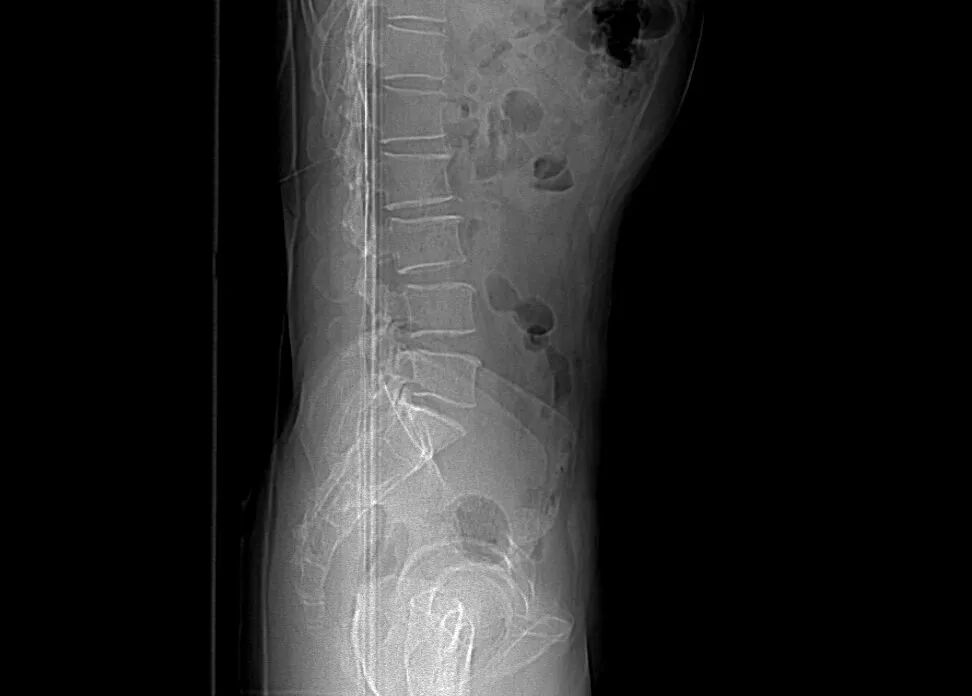

圖5:術(shù)前DR

術(shù)前影像資料